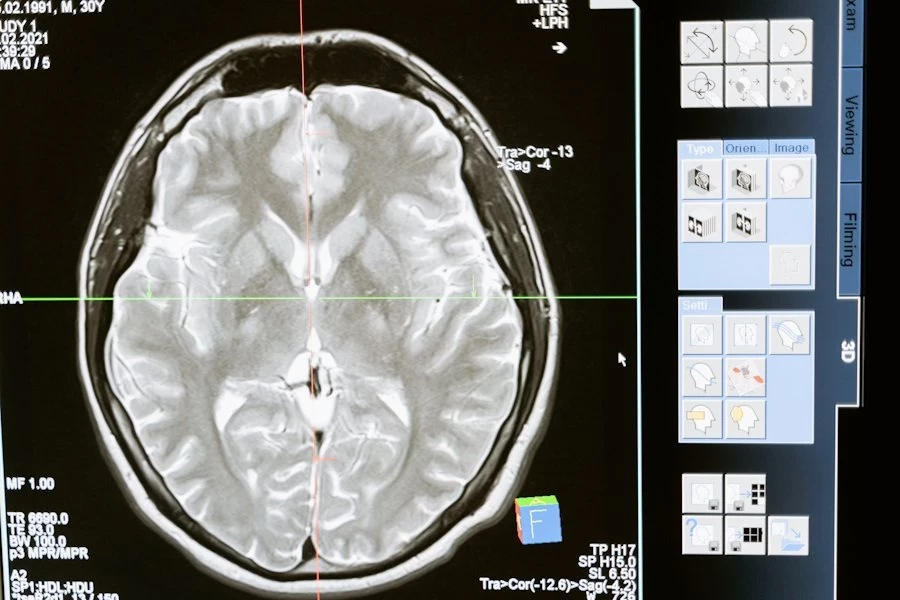

Ситуация усугубилась после заявления одного из ведущих канадских ученых Майкла Култхарта, который сообщил, что ему запретили продолжать исследования болезни. Култхарт предполагает, что основным триггером могут быть факторы окружающей среды или их комбинация, вызывающие цепочку нейродегенеративных синдромов, подобных болезни Альцгеймера и болезни Паркинсона. Он подчеркнул, что данное заболевание не вписывается в стандартные диагностические рамки, что позволяет политикам избегать обсуждения проблемы и ограничивать доступ ученых к исследованиям.